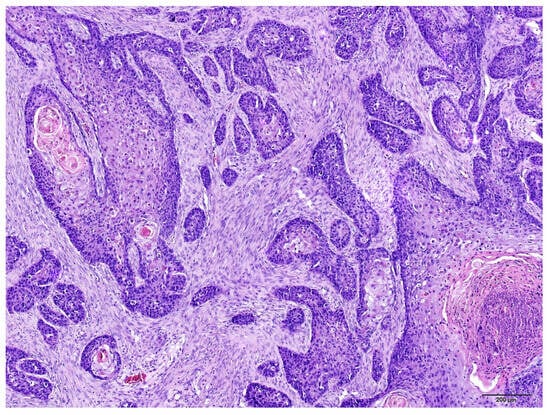

3. Results